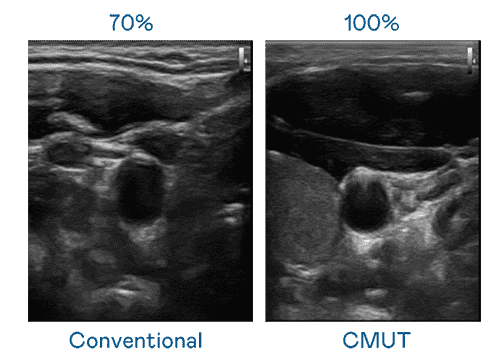

CMUT 技术是一种用电容式微机电元件来产生超音波讯号的技术。。。。与传统 PZT 压电式技术相比,,,,CMUT 频宽增加 30%,,更宽频的超音波讯号让影像解析度大幅提升,,,,是实现高影像品质医疗超音波扫描、、、促进精准医疗发展的关键技术。。。

大频宽带来超清晰影像

超音波影像的解析度高低,,,,首先取决于探头能发出的讯号频宽。。开云电子 CMUT 可提供高清晰的超音波讯号,,提供高频宽、、、、高灵敏度、、、影像纹理细节更高的超音波影像,,,,协助医护人员缩短影像判读时间及利用精准的医疗影像进行诊断。。